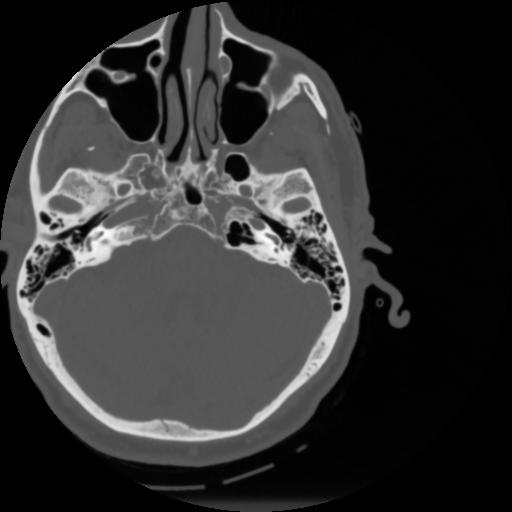

4 CEREBRO,,Vol,0.5,CEREBRO,,